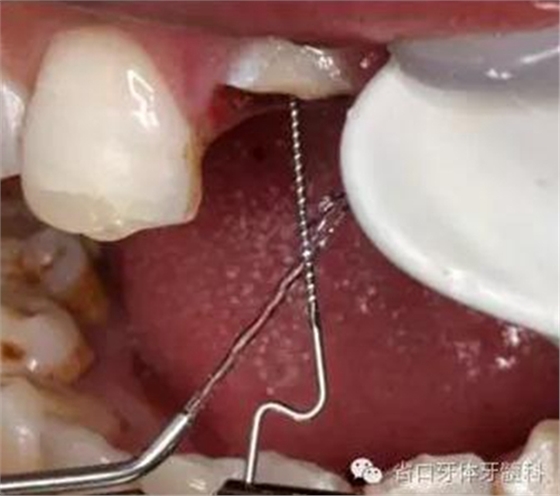

圖12. 超聲蕩洗纖維樁道

圖13. 纖維樁及斷冠粘接固定